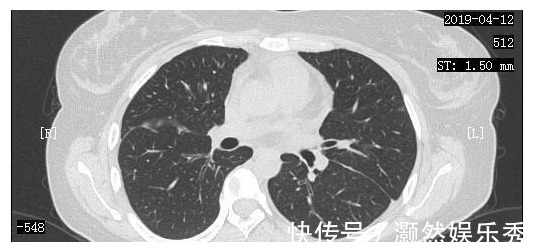

我院肿瘤科医生根据小周的一般情况,也马上下了病危,提醒小周家属,随时可能出现去世的可能。在小周父母很伤心的时候,反而是小周心态积极,安慰父母:我们就积极治疗吧,能够到哪一天就到哪一天吧。同时,根据小周的病情状况,肿瘤科医生也马上制定了治疗方案,给予了小周化疗以及靶向治疗,通过调整靶向药物,小周从2018年9月23日开始口服某靶向药物治疗。经过治疗,小周的一般情况居然逐渐好转起来,同时也顺利出院回家进行调养,到2019年4月12日,小周又再次在我院复查了CT,我们惊喜地发现,她双肺的病灶明显减少,甚至几乎看不到了。